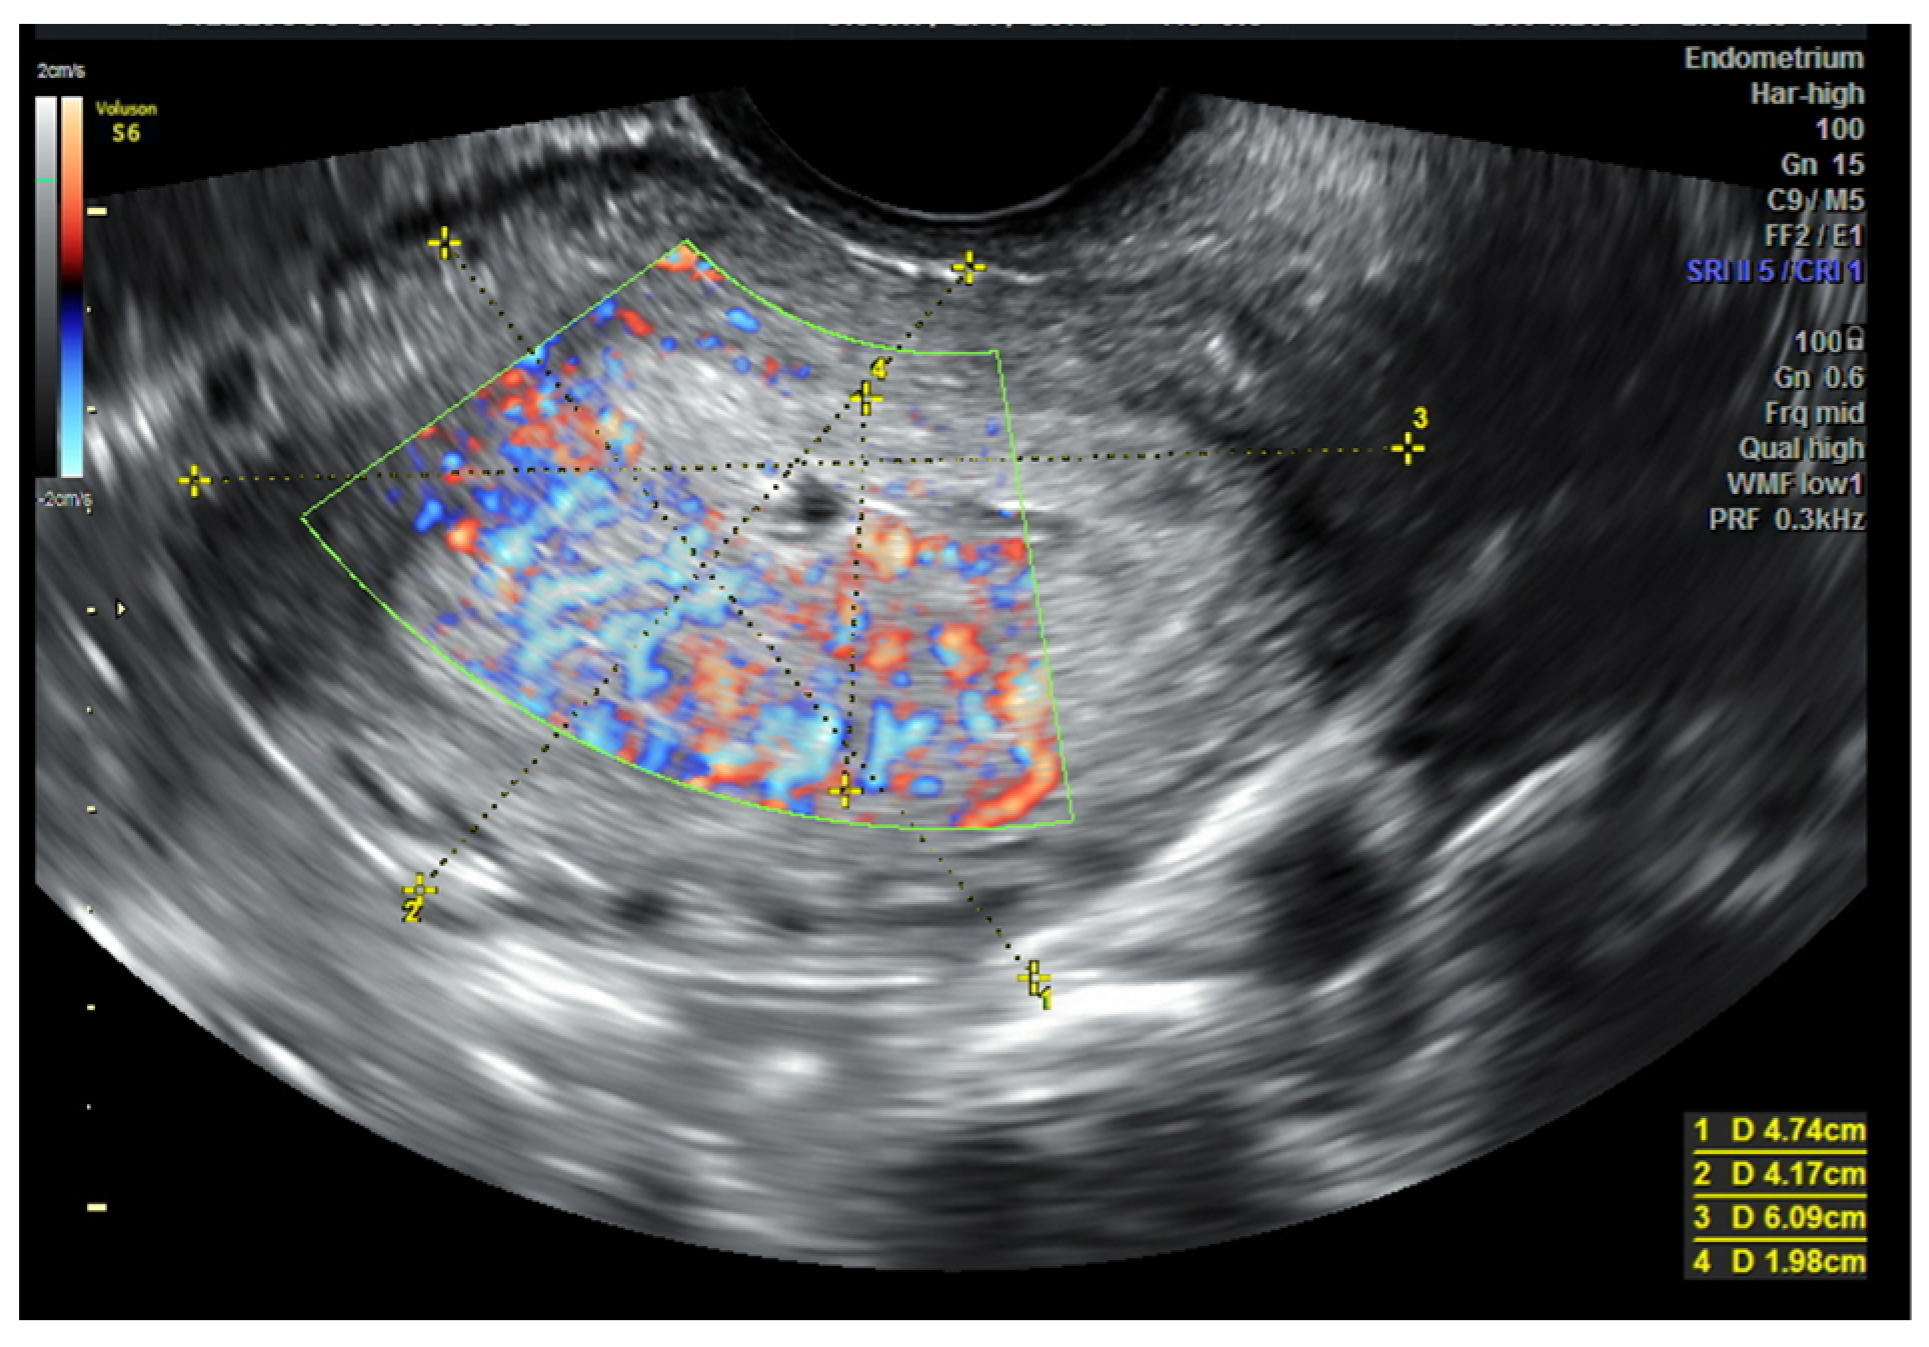

3.1. USG (Ultrasonography) and MRI (Magnetic Resonance Imaging)

- Eriksson, L.S.; Lindqvist, P.G.; Rådestad, A.F.; Dueholm, M.; Fischerova, D.; Franchi, D.; Jokubkiene, L.; Leone, F.P.; Savelli, L.; Sladkevicius, P.; et al. Transvaginal ultrasound assessment of myometrial and cervical stroma invasion in women with endometrial cancer: Interobserver reproducibility among ultrasound experts and gynaecologists. Ultrasound Obstet. Gynecol. 2015, 45, 476–482. [Google Scholar] [CrossRef]

- Capozzi, V.A.; Rosati, A.; Rumolo, V.; Ferrari, F.; Gullo, G.; Karaman, E.; Karaaslan, O.; HacioĞlu, L. Novelties of ultrasound imaging for endometrial cancer preoperative workup. Minerva Med. 2021, 112, 3–11. [Google Scholar] [CrossRef] [PubMed]

- Epstein, E.; Van Holsbeke, C.; Mascilini, F.; Måsbäck, A.; Kannisto, P.; Ameye, L.; Fischerova, D.; Zannoni, G.; Vellone, V.; Timmerman, D.; et al. Gray-scale and color Doppler ultrasound characteristics of endometrial cancer in relation to stage, grade and tumor size. Ultrasound Obstet. Gynecol. 2011, 38, 586–593. [Google Scholar] [CrossRef]

- Fischerova, D.; Frühauf, F.; Pinkavova, I.; Kocián, R.; Nemejcova, K.; Dusek, L.; Cibula, D. Factors affecting sonographic preoperative local staging of endometrial cancer. Ultrasound Obstet. Gynecol. 2014, 43, 575–585. [Google Scholar] [CrossRef]